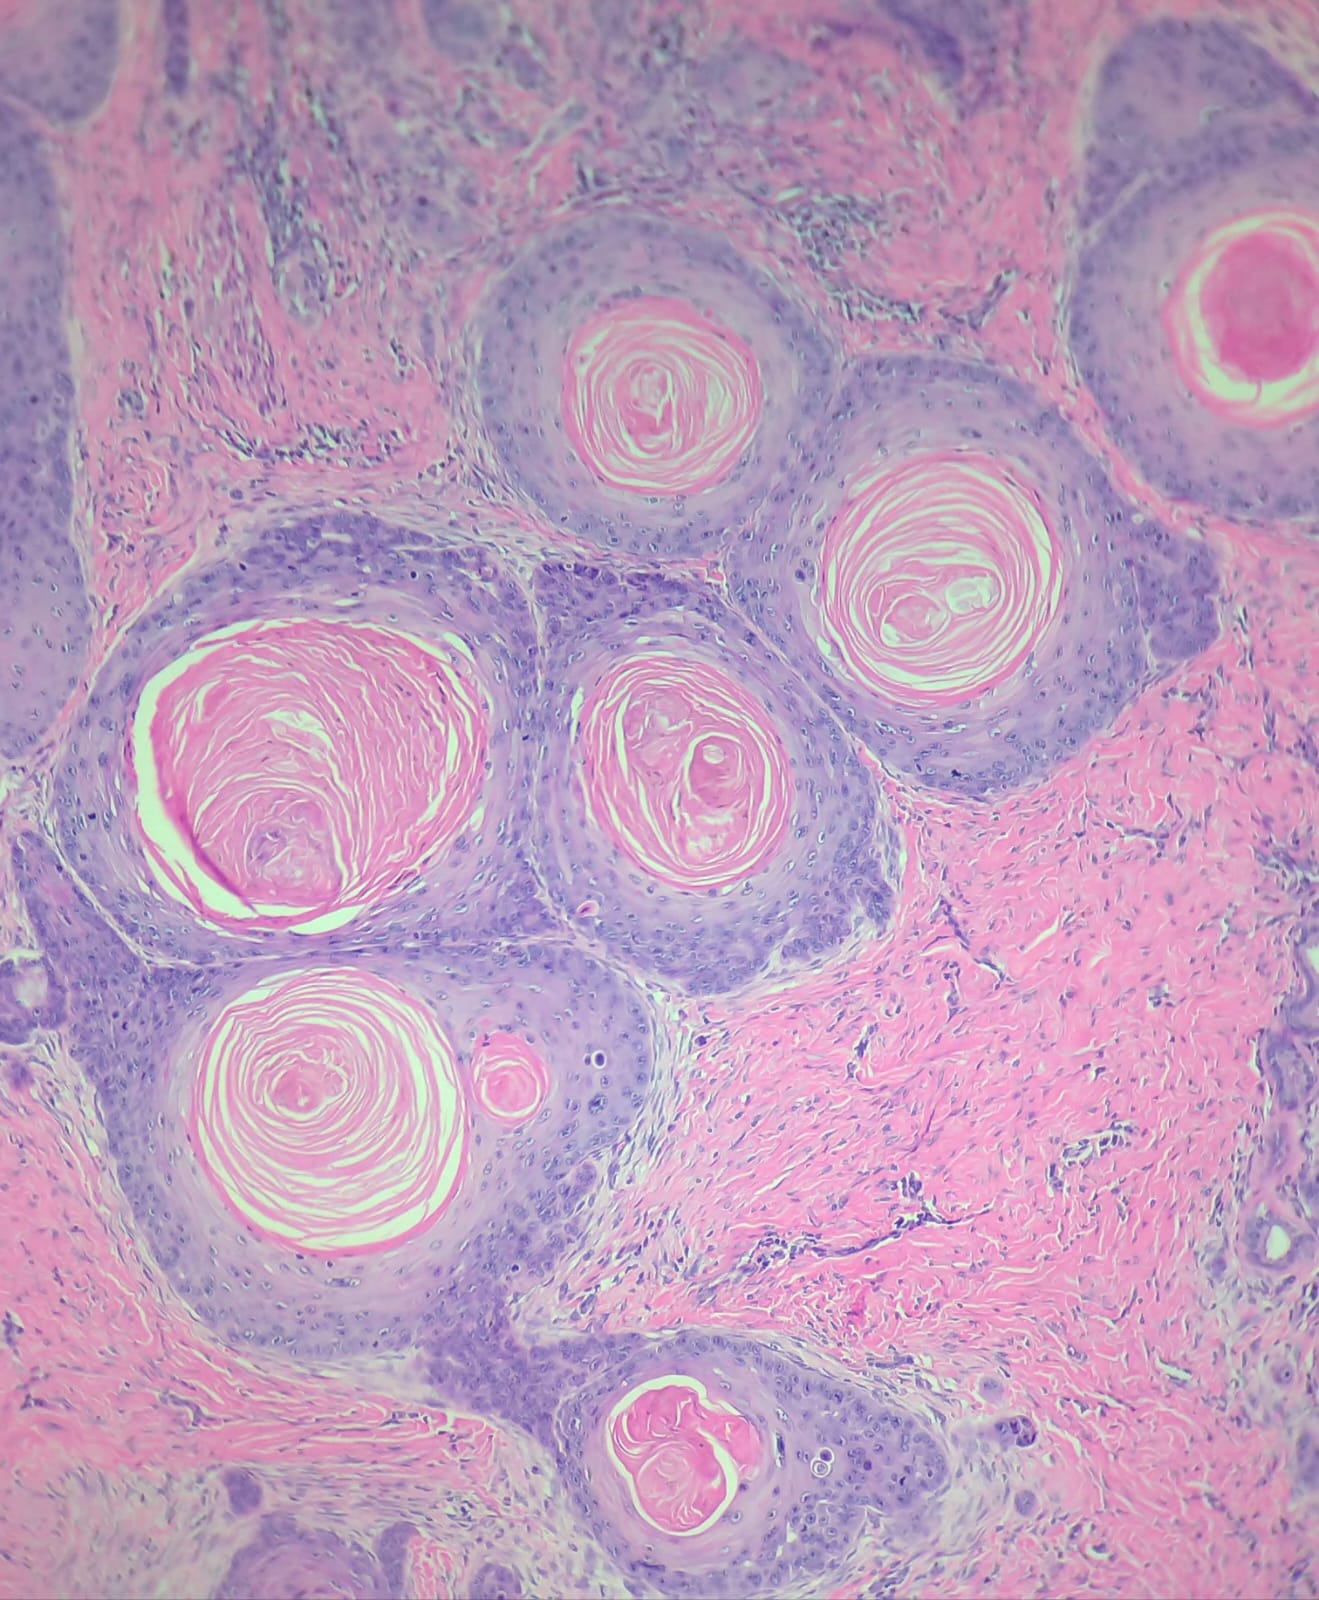

Além de atuar nas áreas de Citopatologia, Histopatologia, Cell Block e Necropsia. O CDVetRio conta com serviço pioneiro e diferenciado de análise histopatológico no transcirúrgico.

Através do método de congelação no transcirúrgico, trabalha-se com a possibilidade de estabelecer margens cirúrgicas livres de neoplasia. A congelação permite cortar o tecido fresco, preparando-o para o exame microscópico e observação no momento da cirurgia, possibilitando além da análise das margens, um diagnóstico presuntivo, com posterior coleta do material em formalina 10%, processamento para exame histopatológico e diagnóstico morfológico final.

análise microscópica de tecidos para detecção de alterações em sua morfologia.

Realizações de colorações especiais por método histoquímico estão inclusas no preço caso necessárias. Para materiais que necessitem de descalcificação pode ser acrescido serão acrescidos 3 dias úteis ao prazo.

- Oncopatologia

- Dermatopatologia